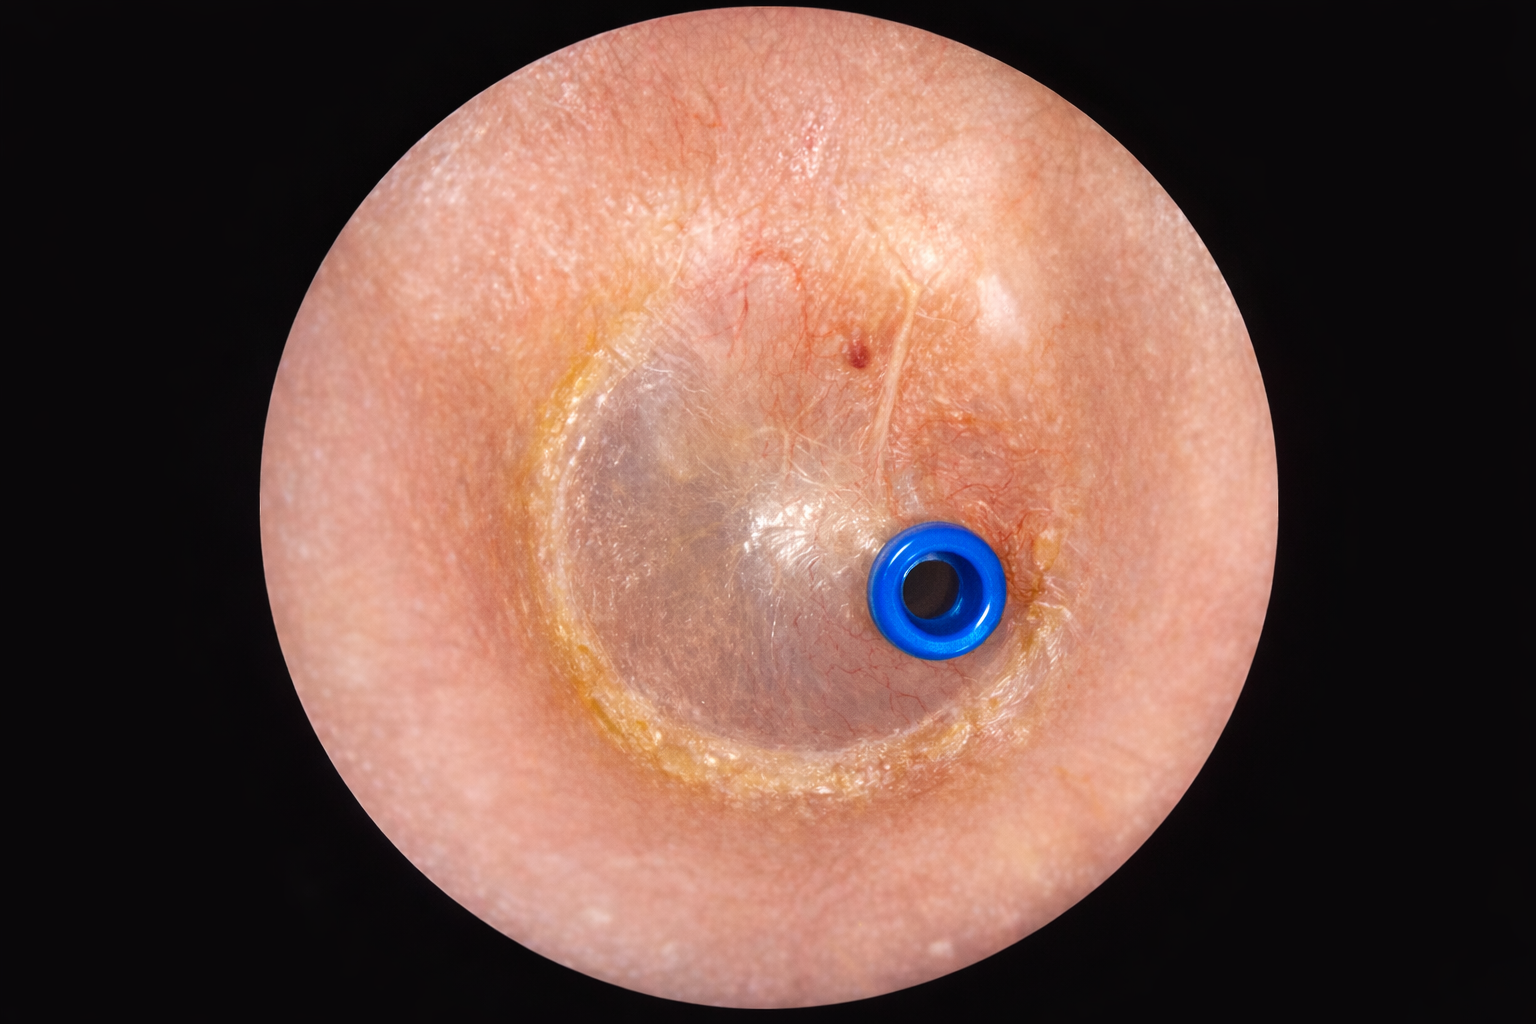

滲出性中耳炎チューブ留置術後

右滲出性中耳炎チューブ留置術後(AIで作成)

右鼓膜に青いチューブが入っています。 鼓膜切開を繰り返しても治らない場合に入れて約1年間入れておきます。